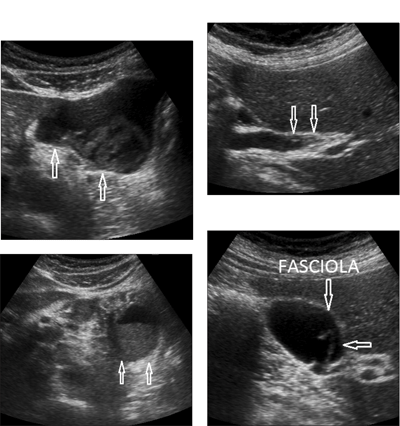

Huỳnh Hồng Quang và Nguyễn Văn Khá (2007) báo cáo một ca lạc chỗ ở cơ thẳng bụng bên (P) của một phụ nữ 39 tuổi sống tại Vũng Tàu, tiền sử trước đó 2 tháng có bị áp xe gan do F. gigantica được điều trị khỏi bằng triclabendazole, hiện nay có triệu chứng ngứa và ban trườn nhiều đợt tại vị trí cơ thẳng bụng, cứ vài ngày lại nổ gồ lên đường di chuyển, đỏ da và ngứa, siêu âm phát hiện hình ảnh áp xe cơ, xét nghiệm ELISA dương tính và bạch cầu ái toan tăng (33,4%), điều trị khỏi bằng thuốc triclabendazole, hình ảnh áp xe cơ trở về bình thường sau 20 ngày và theo dõi sau 2 năm không thấy tái phát.

Chẩn đoán hình ảnh để xác định nhiễm trùng lạc chỗ vùng phổi - màng phổi ở 5 bệnh nhân. Một bệnh nhân có bụng báng và tràn dịch màng phổi và dịch màng bụng kèm theo tăng bạch cầu eosin tăng cao. Trên các bệnh nhân, trứng SLGL được phát hiện. 2 ca có nốt ở gan và hai ca khác có tổn thương dạng nang ở gan. 3 bệnh nhân có sán non Fasciola sp. trong túi mật. Họ kết luận việc chẩn đoán SLGL dùng siêu âm và huyết thanh học là cần thiết cùng với xét nghiệm phân, đặc biệt trong những ca nhiễm mạn tính và trong nhiễm sán máng S. mansoni tại vùng lưu hành.